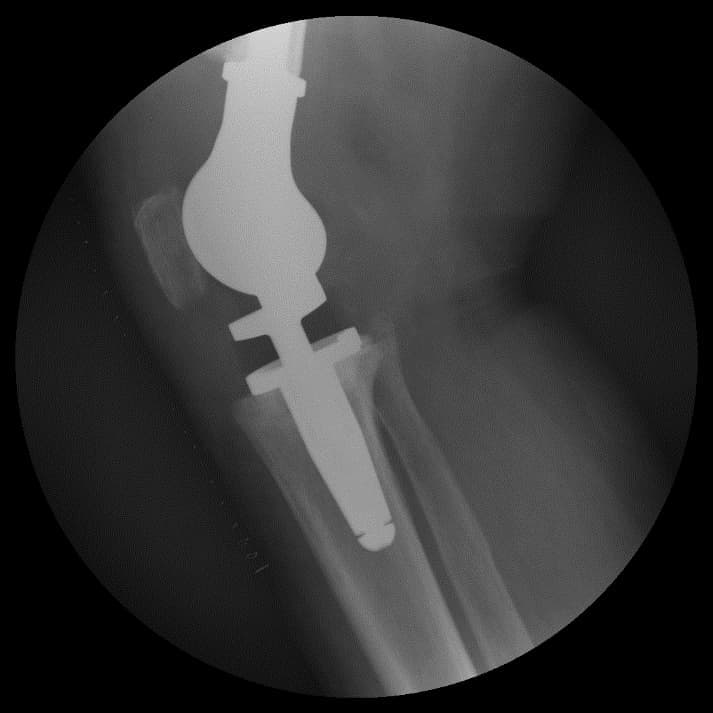

Энэ хиймэл үений онцлог нь дунд чөмөгний гандан хэсгийн доод 1/3 хэсэг, үений булуу хэсгийг бүрэн орлох хавдрын тусгай хиймэл үе юм. Мөн hinge system-тэй.

Үе дайрсан ясны анхдагч хавдар, ясны дутмагшлын үед хийгдэх мэс засалimg34Үе дайрсан ясны анхдагч хавдар, ясны дутмагшлын үед хийгдэх мэс засалimg35

Зураг 3. Мэс заслын дараах рентген зураг. Эгц урд, хажуугаас авсан байдал.

Дунд чөмөг-өвдөгний хавдрын протез, нугас буюу hinge system-тэй. Хиймэл үе - ястай тогтвортой сайн бэхлэгдэх нөхцлийг хангах чөмөгт гол руу орсон уртасгагч – extension stem-тэй хиймэл үе.